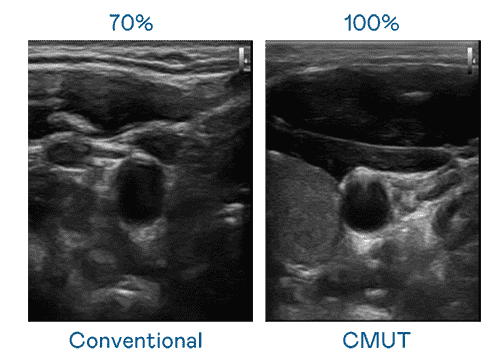

CMUT 技术是一种用电容式微机电元件来产生超音波讯号的技术。。。与传统 PZT 压电式技术相比,,,CMUT 频宽增加 30%,,更宽频的超音波讯号让影像解析度大幅提升,,,,是实现高影像品质医疗超音波扫描、、、促进精准医疗发展的关键技术。。

大频宽带来超清晰影像

超音波影像的解析度高低,,,,首先取决于探头能发出的讯号频宽。。。尊时凯龙 CMUT 可提供高清晰的超音波讯号,,,,提供高频宽、、、、高灵敏度、、、、影像纹理细节更高的超音波影像,,,协助医护人员缩短影像判读时间及利用精准的医疗影像进行诊断。。